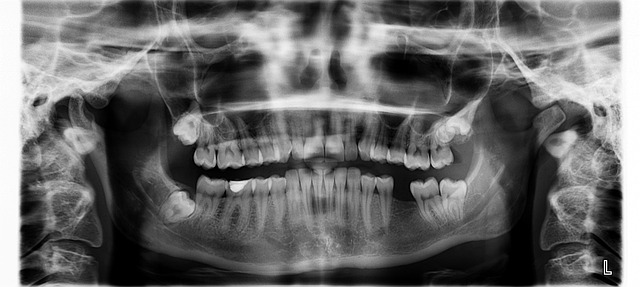

치통은 일상생활에 큰 지장을 주는 통증 중 하나입니다. 대부분의 치통은 충치, 잇몸 질환, 사랑니 문제 등이 원인이며, 진통제를 통해 일시적으로 통증을 완화할 수 있습니다. 이 글에서는 치통에 효과적인 진통제의 종류, 복용법, 주의사항까지 자세히 안내드립니다.